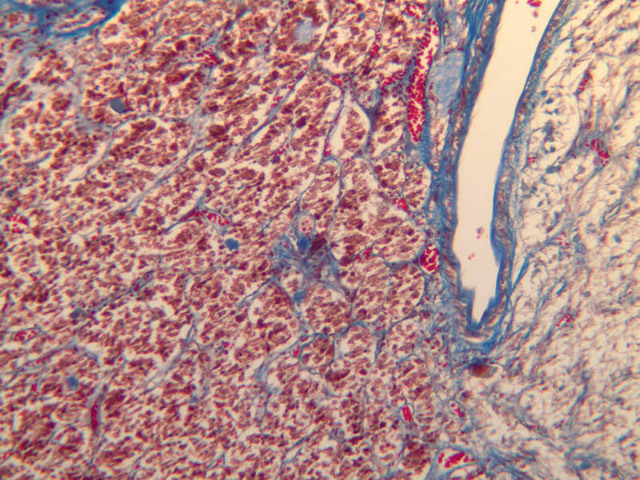

The neurohypophysis arises as an outpocketing of neuroectoderm from the floor of a portion of the brain called diencephalon. It is divisible into the pars nervosa, which forms the posterior portion of the main mass of the pituitary, and the infundibulum, or pituitary stalk. In H&E-stained sections, the neurohypophysis is distinctly eosinophilic. The adenohypophysis (anterior pituitary) has three different types of secretory cells, which are best visualized in the trichrome-stained preparation on slide B-65: (1) acidophils have a reddish staining cytoplasm, owing to the presence of secretory granules. These cells secrete growth hormone (GH) and prolactin (PRL); (2) basophils are slightly larger cells with bluish staining granules present in the cytoplasm. These cells tend to occur in small groups or clusters. Basophils are responsible for the production of thyroid stimulating hormone (TSH), adrenocorticotrophic hormone (ACTH), and the gonadotrophic hormones follicle stimulating hormone (FSH) and luteinizing hormone (LH ); (3) chromophobes or C cells are smaller cells and have only a small amount of poorly staining cytoplasm (B-63, H&E [2.5x-labeled, 10x, 20x, 40x-labeled] [2.5x, 10x, 20x, 40x-labeled]; B-65, trichrome [2.5x, 10x, 20x, 40x-labeled] [2.5x, 10x, 20x, 40x] [10x, 20x, 40x-labeled] [2.5x, 10x, 20x, 40x] [2.5x, 10x, 20x, 40x]). What is the target organ of each of the hormones produced by the adenohypophysis? Note the rich vascularity of the adenohypophysis. Can you describe the blood supply and its significance?

B63, Pituitary, 2.5x (H&E) B63, Pituitary, 10x Labeled (H&E) B63, Pituitary, 20x (H&E) B54, Pituitary, 2.5x (AF) B54, Pituitary, 10x (AF) B54, Pituitary, 20x (AF) B54, Pituitary, 40x (AF) B65, Pituitary, 2.5x (Trichrome) B63, Pituitary, 2.5x Labeled (H&E) B63, Pituitary, 10x (H&E) B63, Pituitary, 20x (H&E) B63, Pituitary, 40x Labeled (H&E) B63, Pituitary, 2.5x (H&E) B63, Pituitary, 10x (H&E) B63, Pituitary, 20x (H&E) B63, Pituitary, 40x Labeled (H&E) B65, Pituitary, 2.5x (Trichrome) B65, Pituitary, 10x (Trichrome) B65, Pituitary, 20x (Trichrome) B65, Pituitary, 40x Labeled (Trichrome) B65, Pituitary, 2.5x (Trichrome) B65, Pituitary, 10x (Trichrome) B65, Pituitary, 20x (Trichrome) B65, Pituitary, 40x (Trichrome) B65, Pituitary, 10x (Trichrome) B65, Pituitary, 20x (Trichrome) B65, Pituitary, 40x Labeled (Trichrome) B65, Pituitary, 2.5x (Trichrome) B65, Pituitary, 10x (Trichrome) B65, Pituitary, 20x (Trichrome) B65, Pituitary, 40x (Trichrome) B65, Pituitary, 2.5x (Trichrome) B65, Pituitary, 10x (Trichrome) B65, Pituitary, 20x (Trichrome) B65, Pituitary, 40x (Trichrome) B64, Pituitary, 2.5x (AF) B64, Pituitary, 10x (AF) B64, Pituitary, 20x (AF) B64, Pituitary, 40x (AF) B63, Pituitary, 2.5x (H&E) B63, Pituitary, 10x (H&E) B63, Pituitary, 20x (H&E) B63, Pituitary, 40x (H&E) B65, Pituitary, 2.5x Labeled (Trichrome) B65, Pituitary, 10x (Trichrome) B65, Pituitary, 20x (Trichrome) B65, Pituitary, 40x (Trichrome) B65, Pituitary, 2.5x Labeled (Trichrome) B65, Pituitary, 10x (Trichrome) B65, Pituitary, 20x (Trichrome) B65, Pituitary, 40x (Trichrome) B64, Pituitary, 2.5x (AF) B64, Pituitary, 10x (AF) B64, Pituitary, 20x (AF) B64, Pituitary, 40x Labeled (AF) B64, Pituitary, 2.5x (AF) B64, Pituitary, 10x (AF) B64, Pituitary, 20x Labeled (AF) B64, Pituitary, 40x (AF)